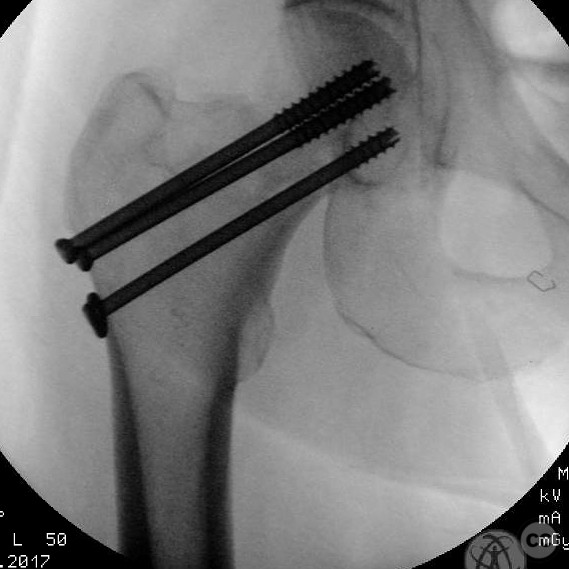

Anatomical surgical approach:  A percutaneous approach was utilized, involving small stab incisions for the insertion of guide wires and cannulated screws. Fluoroscopic imaging was employed to ensure proper alignment and fixation.

The surgeon emphasized the importance of achieving an anatomical reduction and avoiding varus malalignment during fixation. The decision to pursue percutaneous fixation was influenced by the patient's high risk for complications with arthroplasty due to his comorbidities and lifestyle factors. The potential for conversion to hemiarthroplasty was considered if fixation failed.

Orthopaedic implants used:   Cannulated screws